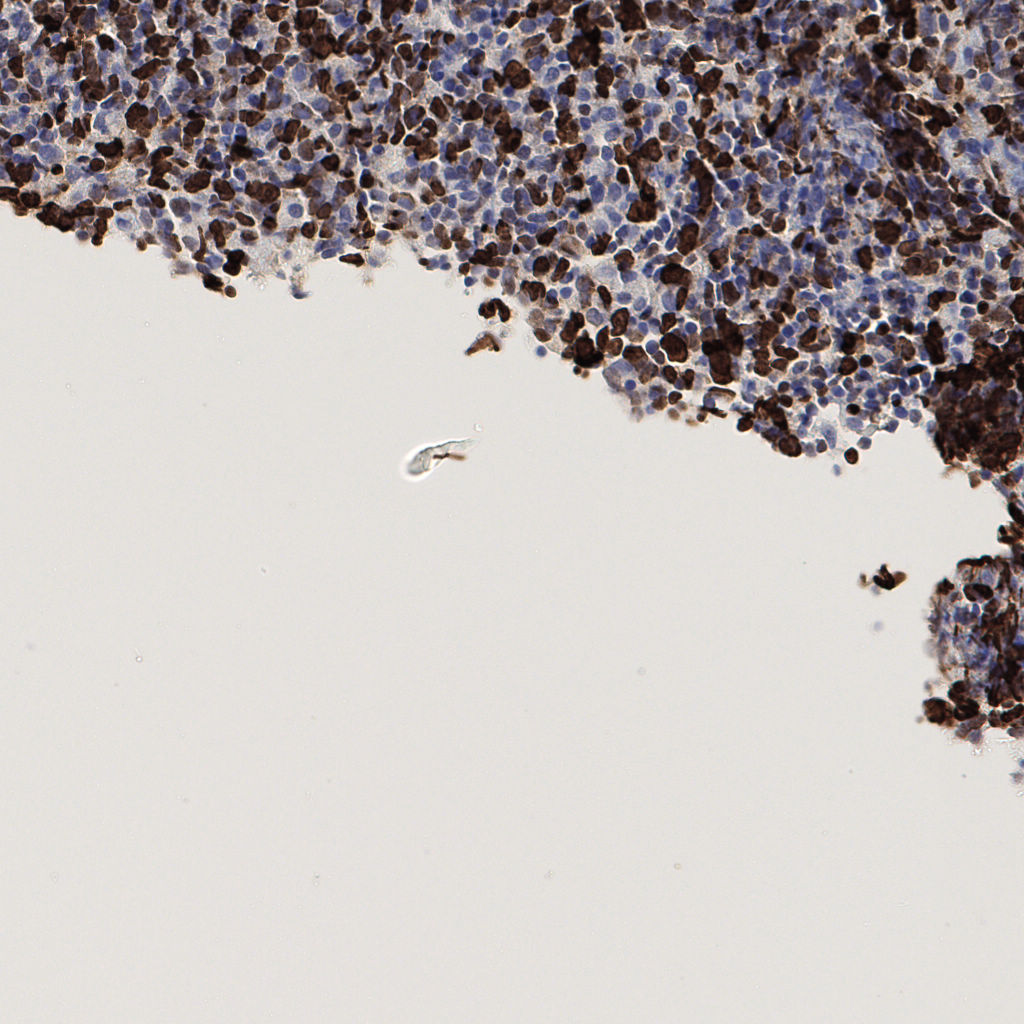

7.85%

Ki67 指数

阴 1104 阳 94

总切片 1953

有效 288

已标记 288

有效率 15%